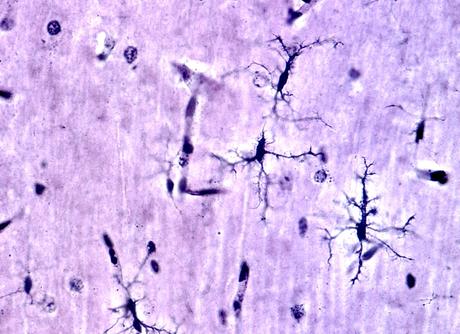

En apparence, la couche la plus externe du cerveau humain, appelée cortex, est un labyrinthe de plis tissulaires. Les sommets ou surfaces surélevées de ces plis, appelés gyri, jouent un rôle important dans le bon fonctionnement du cerveau. Une mauvaise gyrification ou formation de gyri a déjà été impliquée dans différents troubles neurologiques, dont la dépression majeure.

Cet index est une mesure du repliement cortical, dérivée des scintigraphies cérébrales, et qui représente en pratique le rapport entre les surfaces courbes et les surfaces lisses du cortex dans une zone d'intérêt donnée.

L’étude a ainsi comparé les valeurs de l’IGL de plusieurs régions corticales du cerveau de patients atteints de dépression majeure avec cl’IGL de témoins en bonne santé. Les données de neuroimagerie utilisées pour comparer et analyser les 2 groupes ont été obtenues à partir d'IRM.

- les valeurs de l’IGL de plusieurs régions corticales du cerveau de patients atteints de dépression majeure suggèrent une « hypogyrification » c’est-à-dire une diminution du repliement cortical vs les personnes en bonne santé ;

- les patients atteints de dépressions ont des valeurs d’IGL significativement plus faibles dans 7 des 66 régions corticales évaluées dans les 2 hémisphères du cerveau ;

- chez ces patients, l'hypogyrification la plus significative est observée dans la pars triangularis gauche, une zone du gyrus frontal inferieur gauche, qui pourra donc être plus spécifiquement analysée à l’imagerie.

Alors que les régions corticales évaluées dans l’étude affectent la régulation émotionnelle, ces schémas de repliement corticaux anormaux, retrouvés chez les patients atteints de dépression, pourraient tout à fait être associés au dysfonctionnement des circuits neuronaux impliqués dans la régulation émotionnelle, ce qui contribuerait à expliquer la physiopathologie du trouble dépressif.